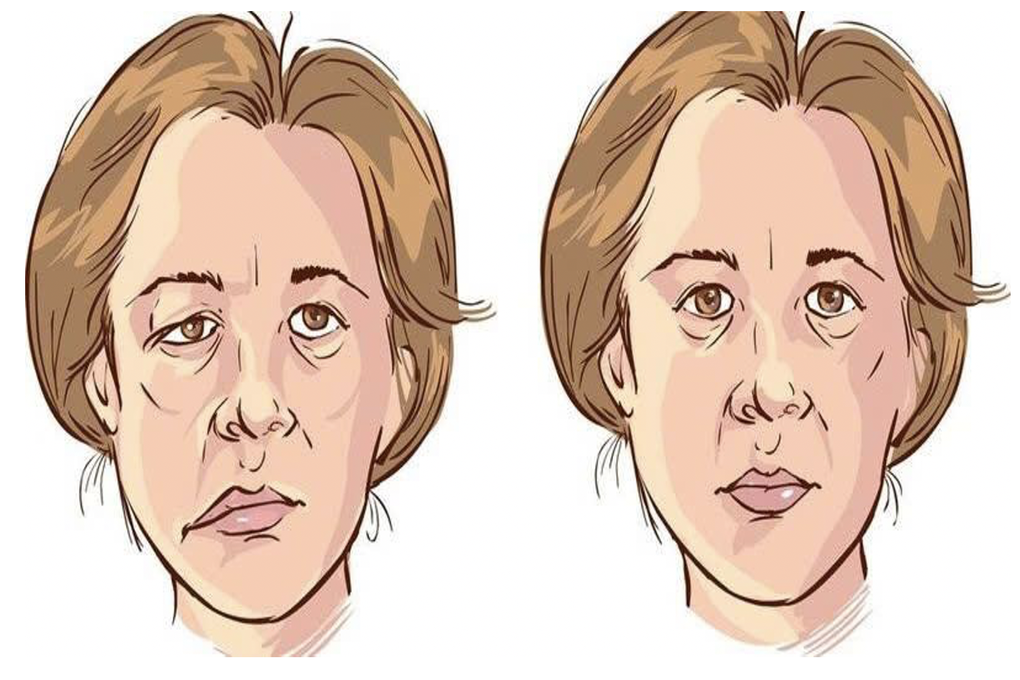

Gương mặt bị co giật do chèn ép dây thần kinh số VII (bên trái) và gương mặt bình thường (Ảnh minh họa: BV).

ThS.BS.CKII Đỗ Anh Vũ, khoa Ngoại Thần kinh – Cột sống, Bệnh viện Đa khoa Quốc tế Nam Sài Gòn, cho biết đây là bệnh lý cần được can thiệp sớm, vì nếu để lâu, các cơn co giật có thể nặng dần, gây biến dạng khuôn mặt cùng những biến chứng nguy hiểm khác, ảnh hưởng thẩm mỹ và tâm lý người bệnh.

Nguy hiểm hơn, trong một số trường hợp, dây thần kinh bị chèn ép quá lâu có thể dẫn đến liệt mặt vĩnh viễn.

Bác sĩ Vũ chia sẻ, co giật nửa mặt là tình trạng một bên cơ mặt co giật không tự chủ, thường khởi phát từ mí mắt rồi lan xuống má và miệng.

Bệnh phổ biến ở người trung niên, không gây đau thể chất nhưng lại khiến người bệnh căng thẳng, mất tự tin, ảnh hưởng lớn đến chất lượng cuộc sống. Nguyên nhân chủ yếu là do mạch máu chèn ép vào gốc dây thần kinh số VII tại cầu não.